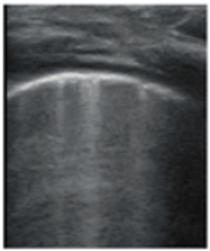

- Subpleural consolidation <1 cm (Figure 4a,b)—31.57%;

| Description of images | Physiological A-lines (upper image) One or two B-lines per intercostal space (marked with yellow arrows) with smooth pleural line (lower image) | More than two B-lines per intercostal space with irregular or thickened pleura | Coalescent/confluent B-lines (upper image)/‘white lung’ or small subpleural consolidations (<1 cm—lower image) | Large consolidations (>1 cm) ± air bronchogram—the image is from a newborn not include in the study with bacterial pneumonia |